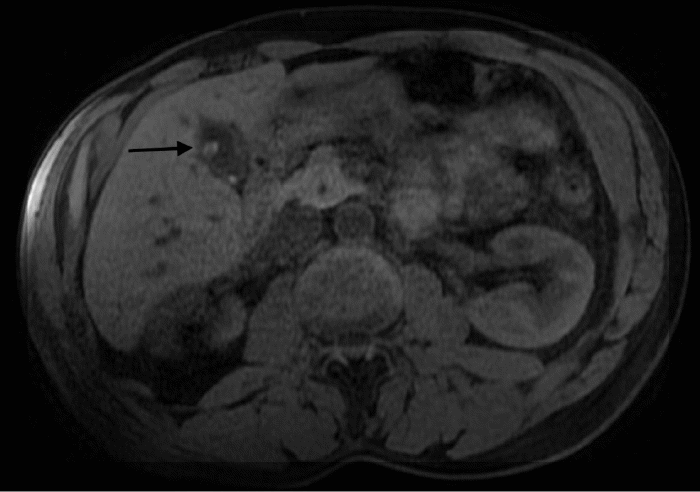

Clinically, the patient reported intermittent abdominal pain, which notably did not worsen postprandially. He denied any history of cholelithiasis, nausea, vomiting, diarrhea, melena, hematochezia, jaundice, or significant weight loss. His social history was significant for daily consumption of three to four cigars and previous heavy alcohol use (12 to 14 drinks per week). Physical examination findings were unremarkable, and laboratory investigations revealed no abnormalities. Based on the patient's symptomatology and the identified gallbladder mass, further diagnostic evaluation with magnetic resonance imaging (MRI) with and without contrast, supplemented by magnetic resonance cholangiopancreatography (MRCP), was pursued one month later. Multiplanar, multisequence MRI demonstrated an 8-millimeter, non-calcified, soft-tissue mass arising from the anterior gallbladder wall, consistent in appearance with a polyp. (Figure 1 and Figure 2). T2-weighted imaging confirmed this finding and also identified small superiorly located gallstones without overt gallbladder wall thickening. The MRCP component of the study yielded unremarkable findings regarding the biliary tree.

Figure 1. MRI without contrast with MRCP. Published with Permission

Figure 2. MRI with contrast with MRCP. Findings: Non-calcified soft tissue mass arising from the anterior wall of the gallbladder. Published with Permission